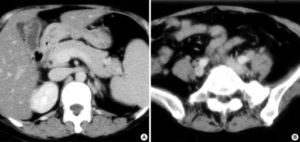

Multiple Organ Dysfunction